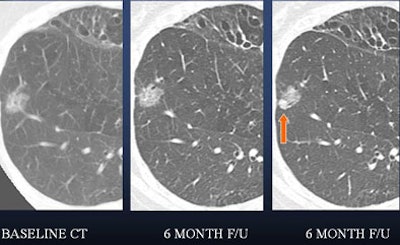

| In a 50-year-old male nonsmoker, a ground-glass nodule is detected in the right lower lobe. At six-month follow-up a solid component could be seen along the inferior aspect of the nodule, suggesting a heightened risk of malignancy. At this point, continued follow-up was deemed too risky, and the lesion was biopsied. The diagnosis was bronchoalveolar cell carcinoma (BAC). |